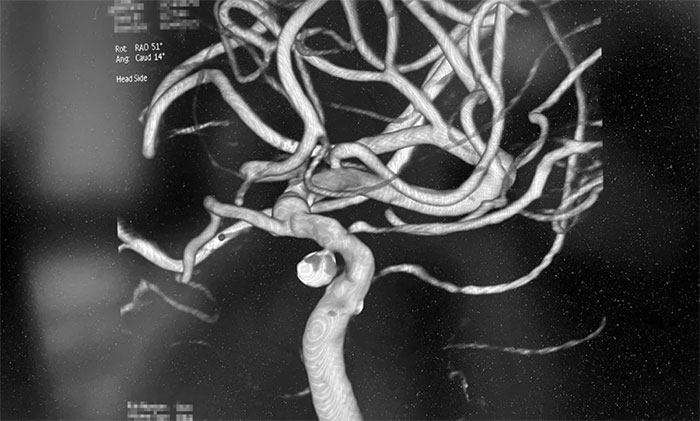

▲ 術(shù)后,成功栓塞動脈瘤并開通血管

術(shù)中,席剛明教授在王貴平博士及醫(yī)護(hù)團(tuán)隊密切配合下,先對左頸內(nèi)動脈C6段動脈瘤進(jìn)行彈簧圈栓塞治療,經(jīng)Echelon-10微導(dǎo)管送入彈簧圈,成籃滿意后暫不解脫;隨后,微導(dǎo)絲引導(dǎo)球囊擴(kuò)張導(dǎo)管頭端置于左側(cè)大腦中動脈M1段,球囊部分覆蓋左頸內(nèi)動脈C6狹窄段,進(jìn)行球囊擴(kuò)張,擴(kuò)張后見左頸內(nèi)動脈C6段狹窄明顯改善,隨后釋放支架于左頸內(nèi)動脈C7段至C4段,造影見左頸內(nèi)動脈、左大腦中動脈、左大腦前動脈顯影可。最后,繼續(xù)栓塞動脈瘤,經(jīng)Echelon-10微導(dǎo)管送入多枚彈簧圈,填塞滿意后解脫,造影見動脈瘤基本不顯影;復(fù)查造影,行3D造影見左頸內(nèi)動脈、左大腦中動脈、左大腦前動脈顯影可;行支架CT見支架成形滿意,行XperCT未見顱內(nèi)出血,手術(shù)圓滿完成。